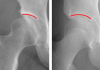

[제주, 제주인의 건강보고서 Ⅷ 건강다이어리] (160)고관절 이형성증

타고난 관절 구조가 원인특히 여성에게 자주 발병퇴행성 관절염으로 이어져조기 진단·맞…

[제주, 제주인의 건강보고서 Ⅷ 건강다이어리] (158)대퇴골두 무혈성 괴사

고관절 통증·절뚝거림 유발음주·스테로이드 주요 원인MRI 검사로 초기 진단 가능단계에 …